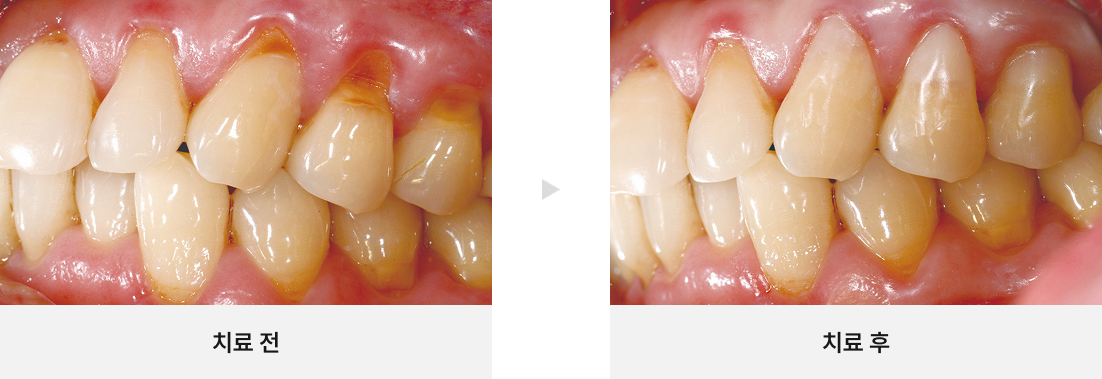

• CASE.05

치경부 마모증이 있는 치아 살리기